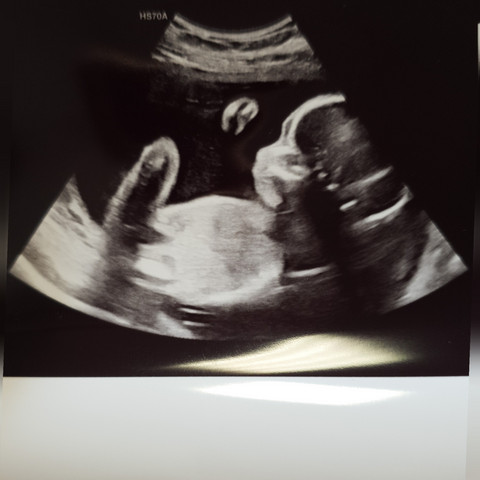

Schwangerschaftswoche ist eine Knospenform Protuberanz zu erkennen die abhängig der Abhebung des Körpers eine Bestimmung des Geschlechts des heranwachsenden Kindes möglich macht. In der 15. HttpwwwyoutubedenukAb wann kann man das Geschlecht des Kindes erkennenEs antwortet.

Laut neuester Studien erfahrener Sonographie-Experten bestimmen die Ärzte das Geschlecht Ihres Babys in der 12. Eine originelle Weise das Geschlecht Ihres Kindes zu enthüllen ist die Getränke Ihrer Gäste zu färben. Schwangerschaftswoche nur zu 46 korrekt.